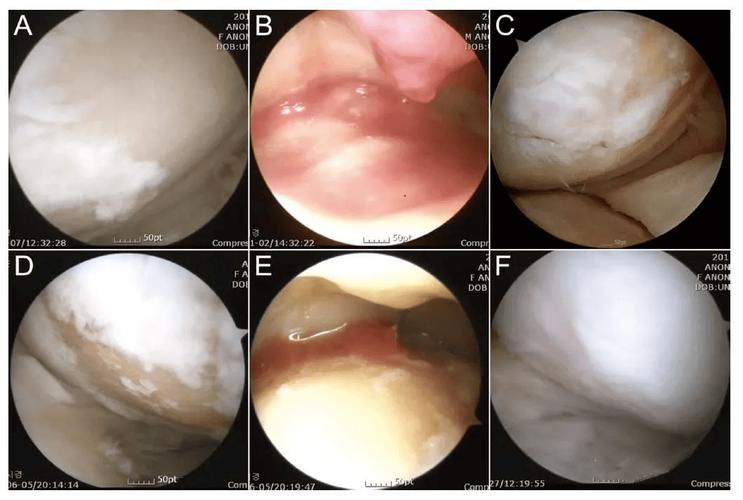

在日本进行的针对膝关节炎开展的干细胞治疗,其核心逻辑不是那种外来的修补方式,而是属于内部赋能的范畴。它依照一条严谨的演绎链条来运作:大前提是人体自身具备自我修复的潜能;小前提是这种自我修复的潜能会随着年龄的增长而处于休眠状态;结论则是,借助高纯度的干细胞回输这种方式,能够重新激活这一机制。在实际的操作过程当中,医生一般是从患者自身的脂肪或者骨髓里面提取间充质干细胞。在符合GMP标准的实验室里面,这些提取出来的细胞会被扩增培养至数千万级别。它们好似一支有过特训经历的工程部队,在被精确注射回遭受损伤的关节腔之后,能够自行地“归巢”到软骨出现磨损的区域。

有一个经典案例,源于《STEM CELLS》期刊的长期随访,针对79名膝关节炎患者施以自体脂肪干细胞治疗,三年后评估表明,关节软骨体积明显增加,疼痛指数平均下降将近60%,这并非神话,乃是经过量化验证的生物学实情。和传统疗法的“灭火”不一样,干细胞疗法所做的是“植树”,它借助旁分泌效应调控局部炎症微环境,还直接分化成软骨细胞,去填补那些被岁月侵蚀的沟壑。